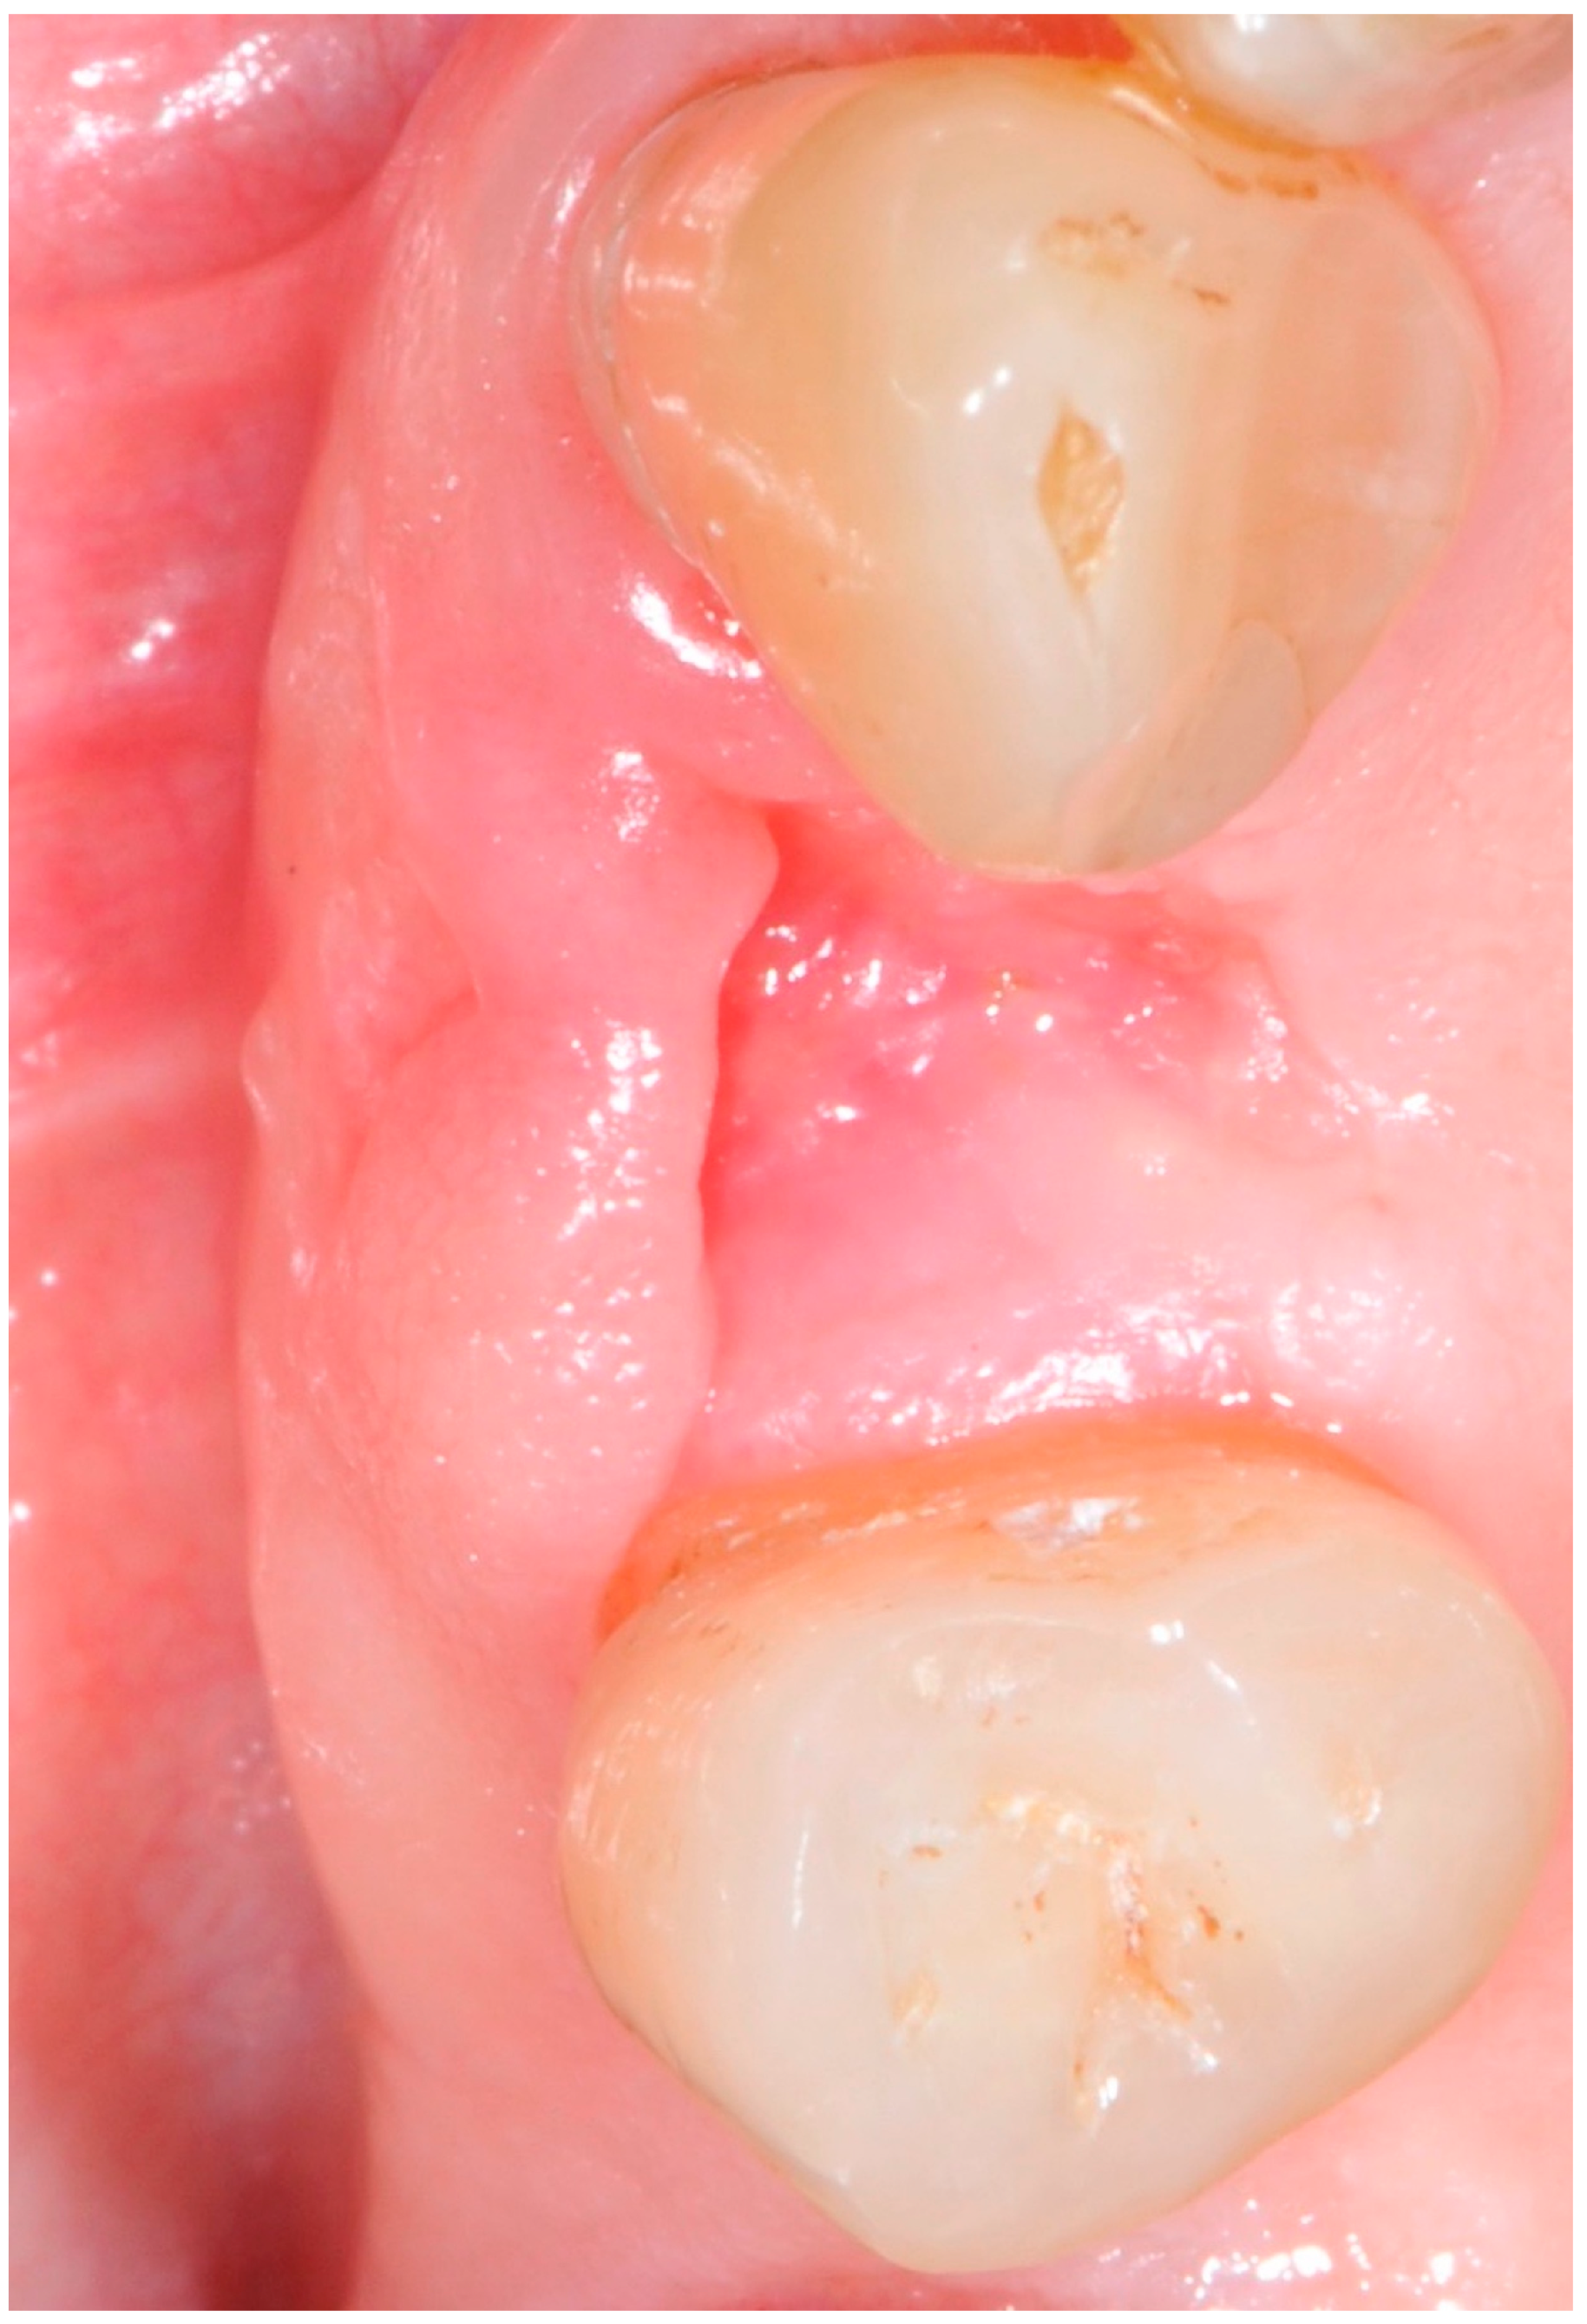

5.4. Surgical Technique